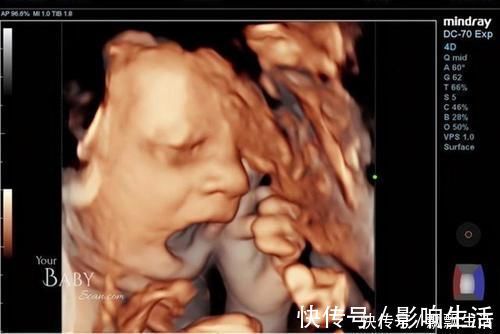

英国孕38周孕妈做彩超,宝宝在肚子里各种搞怪!?

英国的一位孕妈在怀孕38周时去做彩超,在显像下看到了宝宝的可爱样子,宝宝一会儿自己竖中指玩,一会儿又打哈欠,挡着脸玩起来了“捉迷藏”……

由于这是他们的第一个宝宝,看到宝宝的这些神奇举动很兴奋,而且明显的看得出,胎儿已经是个“小宝宝”的样子了,而且在妈妈肚子里还很淘气。

四维彩超,大多是排畸时做,看得会更清楚些,而且还会把当时拍到的胎儿样子,定格下来作为纪念。

于是就可能看到胎宝宝各种“状态”,有的很淘气,各种“做鬼脸”不配合,但也有的比较听话,能很快的顺利做完。